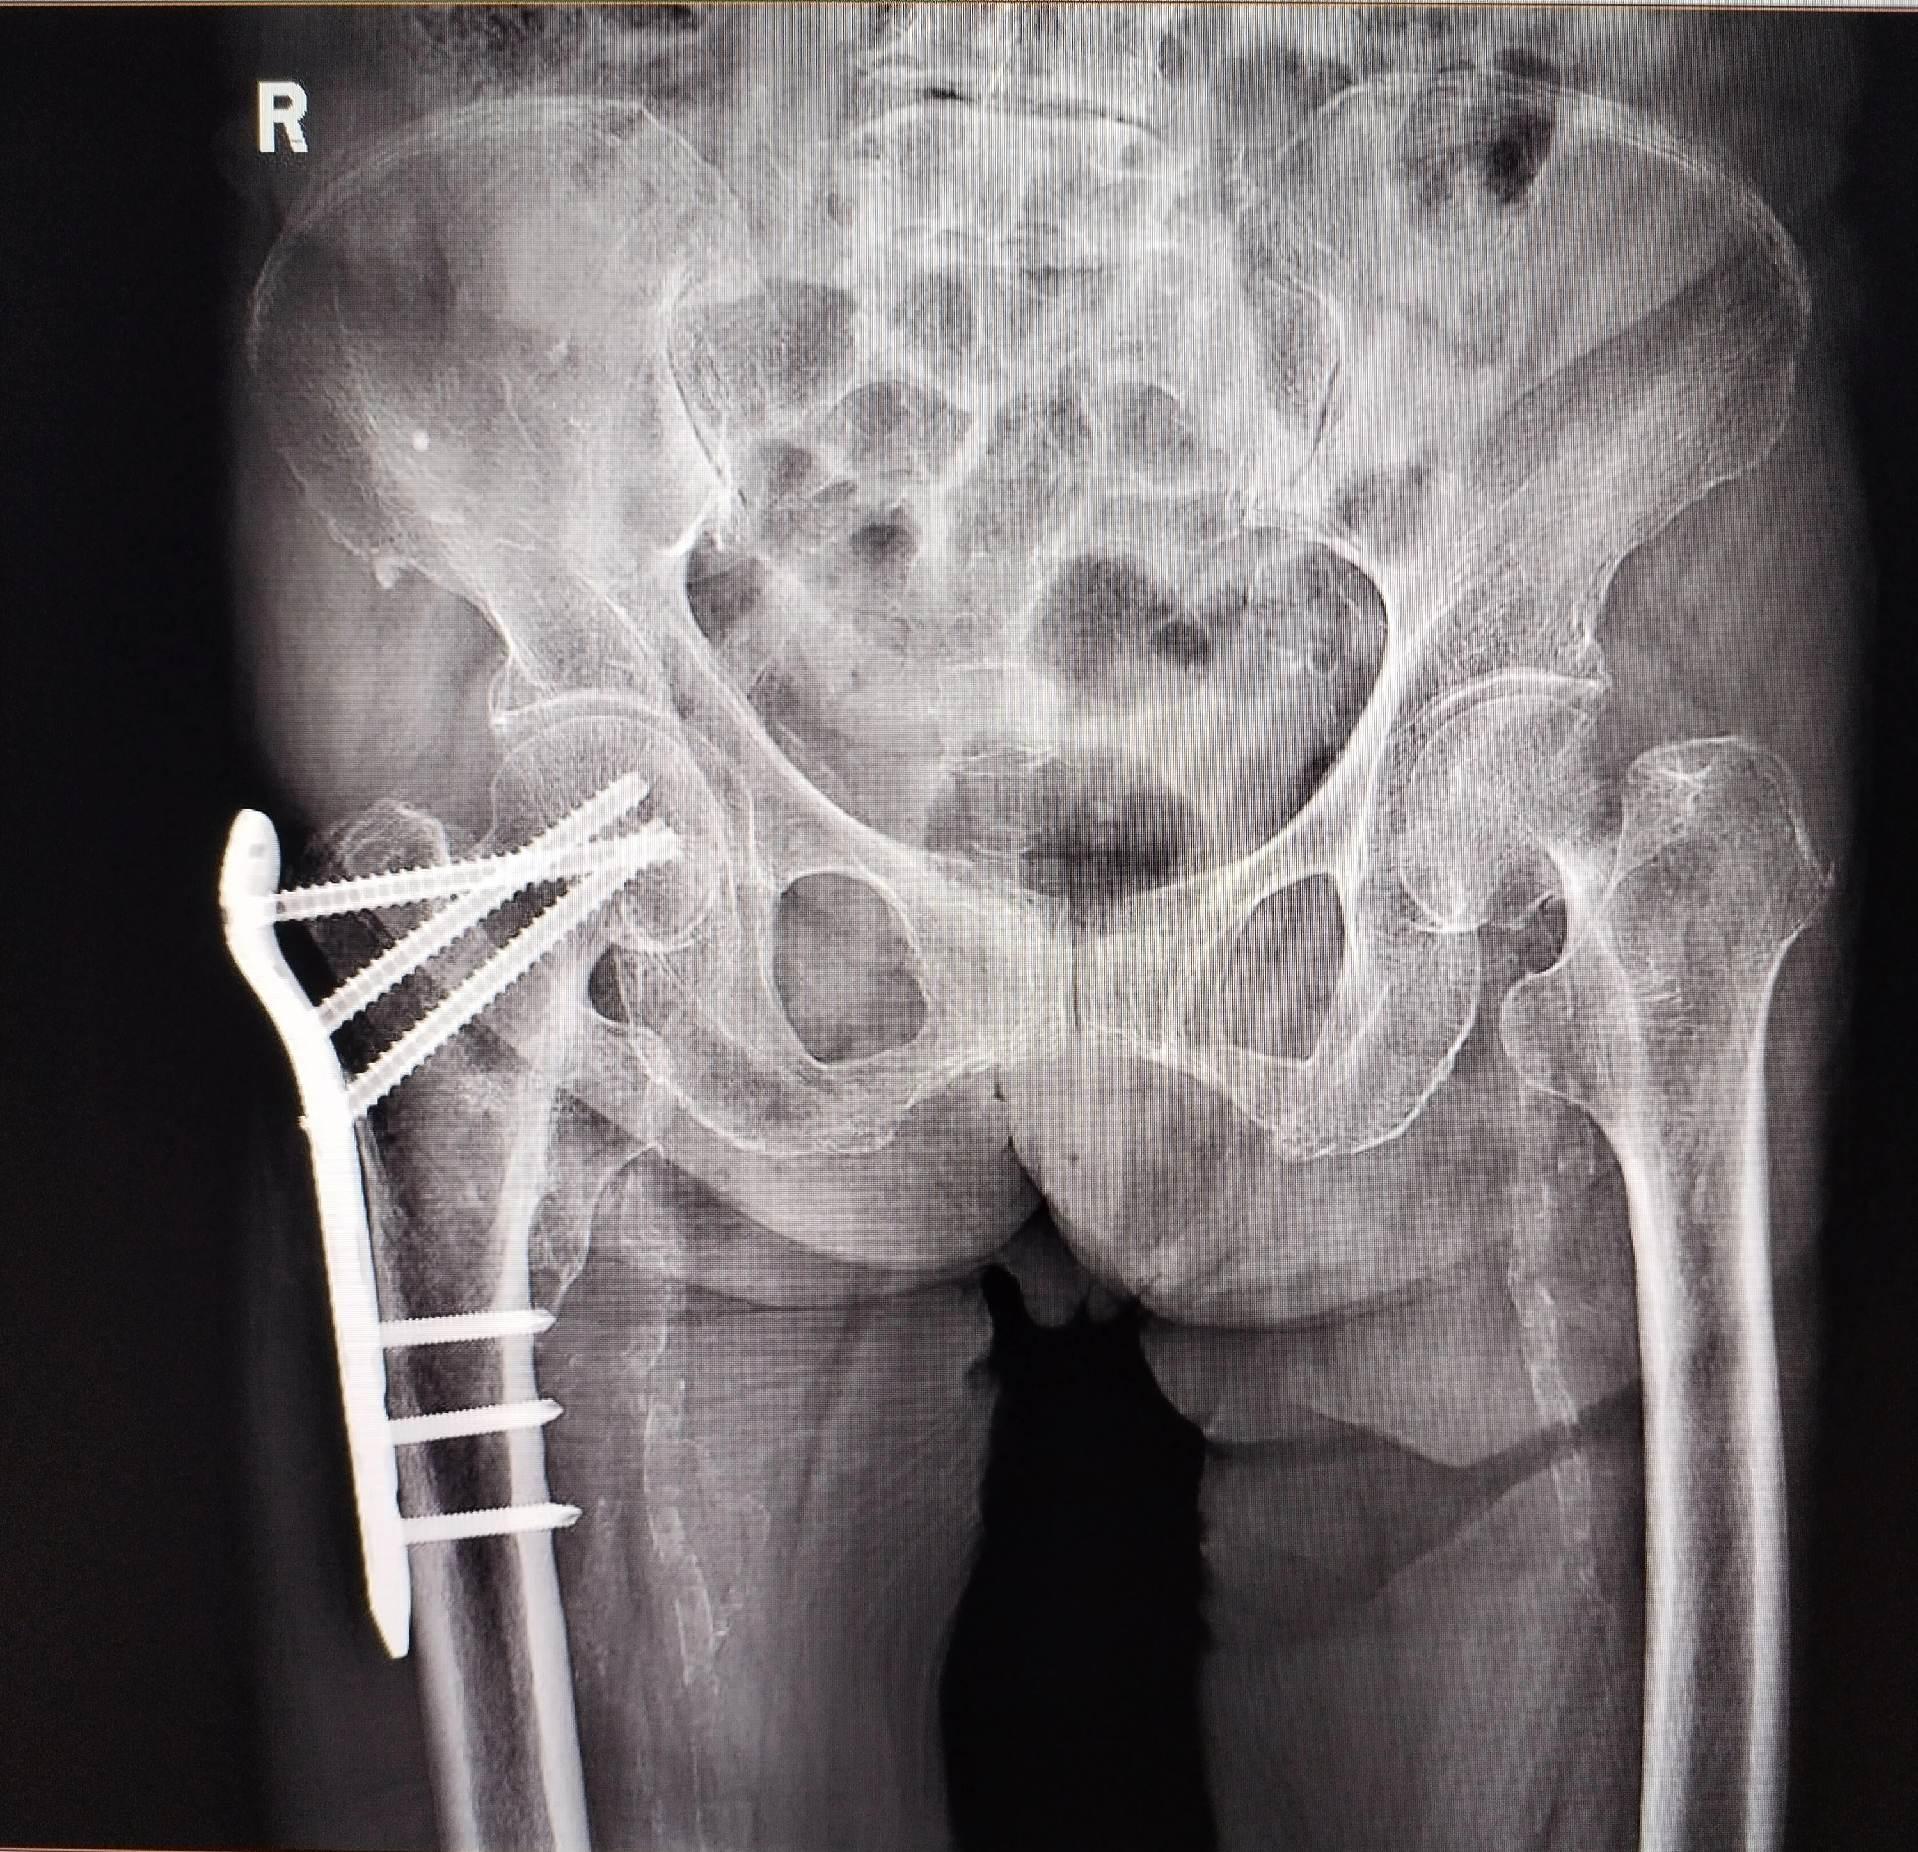

股骨颈骨折。101岁老太太,股骨颈骨折,鬼门关走一遭又回来了。家属的充分理解和支持,相关科室的齐心协力,是手术成功的关键因素🌹髋关节置换

股骨颈骨折。101岁老太太,股骨颈骨折,鬼门关走一遭又回来了。家属的充分理解和支持,相关科室的齐心协力,是手术成功的关键因素🌹